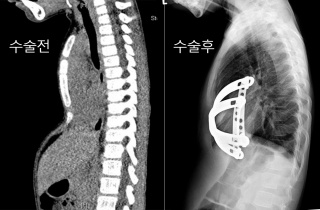

Ä«ÀÚÈ彺ź ¼±Ãµ¼º ÈäºÎ±âÇü ¼Ò³â¿¡ »õ »î ¼±¹°

¿¬¼¼´ëÇб³ °­³²¼¼ºê¶õ½ºº´¿øÀÌ ¼±Ãµ¼º ÈäºÎ±âÇü ÁúȯÀ» ¾Î°í ÀÖ´Â Ä«ÀÚÈ彺ź ¼Ò³â ¾Æ¶ó¶ù±º(7¼¼)À» ÃÊÃ»ÇØ Ä¡·á¸¦ Áö¿øÇß´Ù°í 2017-02-28 19:20:10